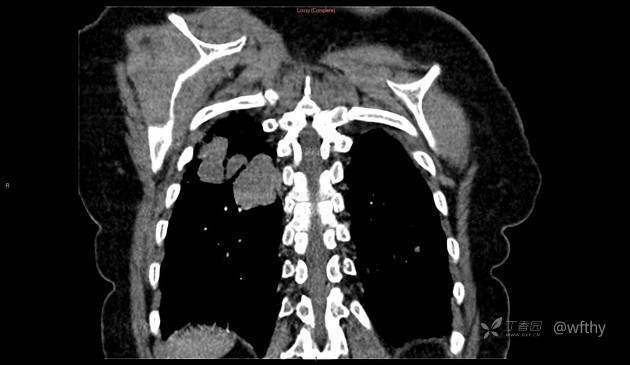

病例女65,头部肿块